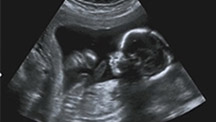

3、B超检查:B超检查是判断早孕最准确的方法,B超检查可以看到孕囊大小、孕囊位置、胎心和胚芽。B超检查还是判断宫内妊娠和宫外妊娠的好方法。